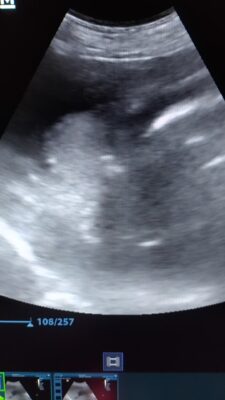

Ik heb hier een chihuahua van bijna 12 jaar, die regelmatig niet wil eten en vaak vlak na het eten onrust en pijn vertoont. Uit het bloedonderzoek komt enkel milde stijging alkalische fosfatase en een milde verhoging van de galzuren. Bij echografie zie ik in de galblaas een hyperechogene structuur die zowel bij ruglig (1e filmpje) als bij…Lees meer